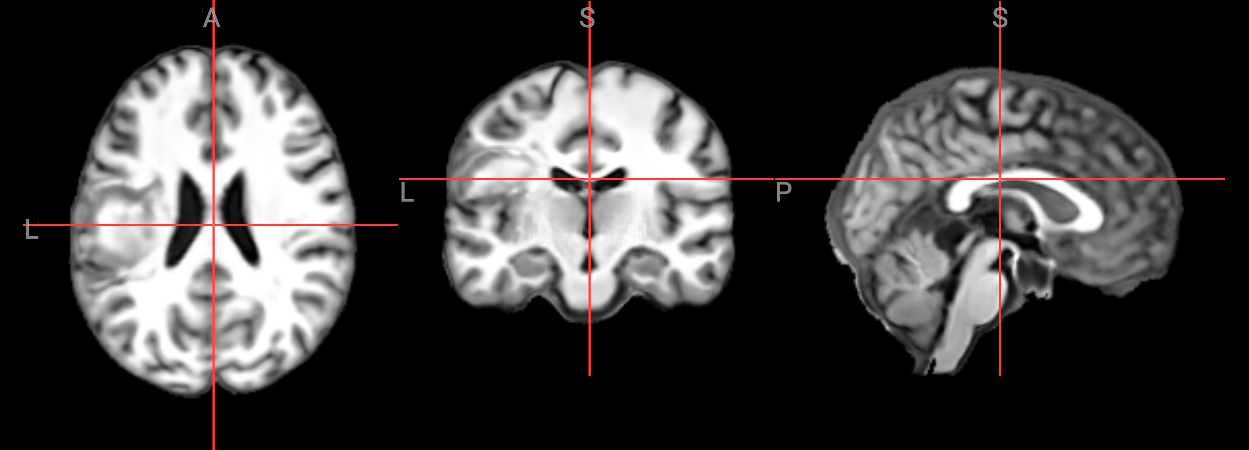

from ipyniivue import NiiVue

nv_subject_space = NiiVue()

nv_subject_space.load_volumes([{"path": input_image}])

nv_subject_space

from IPython.display import Image

Image(filename='../../static/examples/structural_imaging/SYNcro/subject_space.png')

../../_images/56b27f2f062d8107865d28521aa15353a229a01b54efa6bb9c35207c8454f828.png